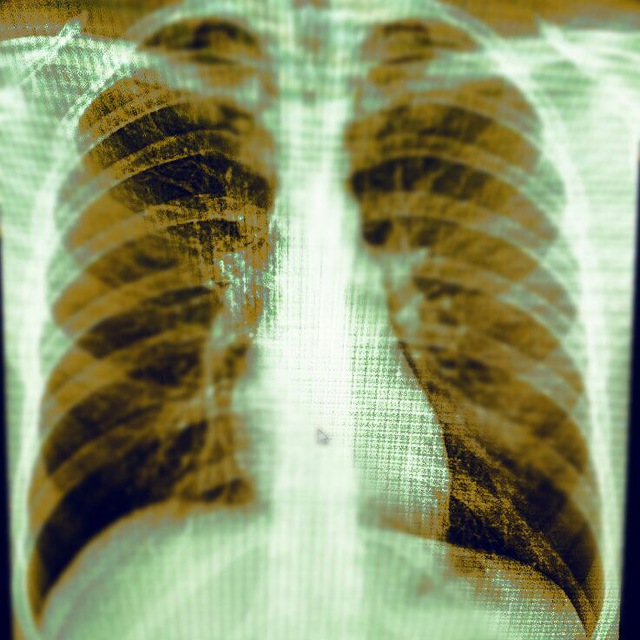

А вот и разгадка:

Можно покрутить? «накиньте» срезов, плиз

Ср или Панкост? Ребро целое? Гидроторакс?

Панкост. Ребро целое, но инфильтрация в спинной канал, отсюда корешковая симптоматика